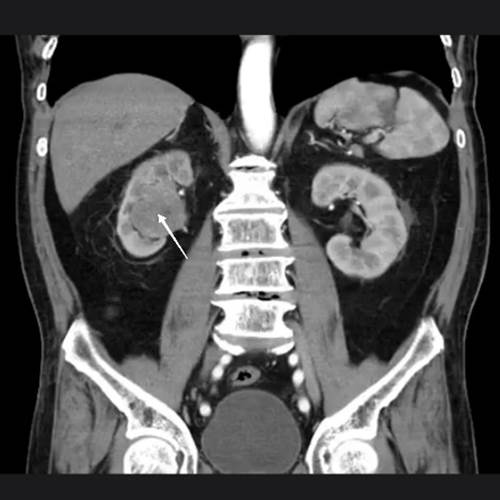

Como antecedentes personales patológicos padece hipertensión arterial sistémica debutante e identificada al ingreso, negando otras enfermedades incluyendo antecedentes quirúrgicos. Inicia su padecimiento con hematuria macroscópica no formadora de coágulos de larga evolución que condiciona síndrome anémico caracterizado por astenia y adinamia, así como palidez de tegumentos. Acude a valoración por área de urgencias donde se le solicitan laboratorios incluyendo biometría hemática (hemoglobina inicial 8.9 g/dL) y urotomografía como parte del protocolo de estudio; en dicha tomografía se muestran imágenes en relación a tumor urotelial en cavidades renales derechas, así como tumor renal izquierdo clasificado como T1a (Imagen 1 y 2).

Unidad renal derecha con imagen sugerente de tumoración piélica derecha que se extiende por uréter ipsilateral (flecha blanca delgada).

Imagen 1 Urotomografía en corte coronal